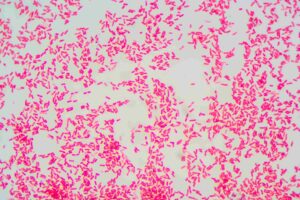

Gut microbiota, intestinal barrier, and sepsis: from dysbiosis to probiotics—what preclinical evidence suggests

Francesco Franceschi from Policlinico Universitario A. Gemelli IRCCS (Roma) focuses on bacterial translocation across a compromised intestinal barrier as a plausible pathway contributing to sepsis.